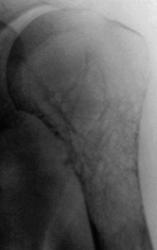

ДО ЛЕЧЕНИЯ,

После лечения (аллотрансплантат и металлоостеосинтез).

Совершенно верно - это консервмированный трансплантант (заказ из ЦИТО)представляет собой проксимальную часть плечевой кости.

А эту пациентку прооперировали в мае 2009г.Сейчас находится на химиотерапевтическом лечении,последний снимок выполнен в сентябре,пока все на месте.